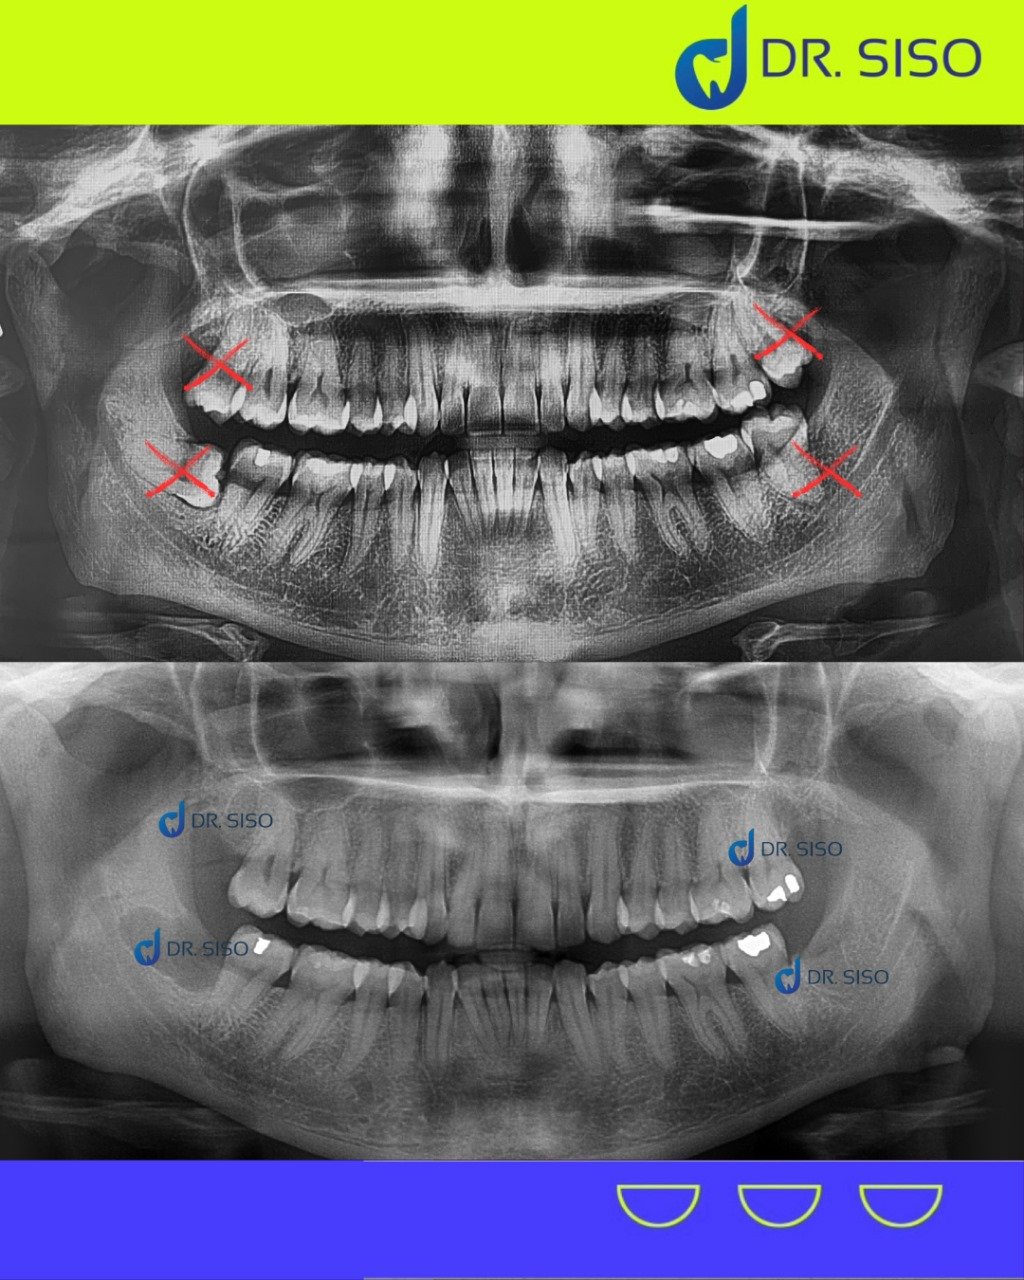

Aquele incômodo no fundo da boca pode ser causado pelos sisos! Quando não há espaço suficiente para nascerem corretamente, eles podem provocar dor, inchaço e até infecções. A extração do siso é um procedimento seguro que evita problemas futuros e alivia o desconforto.

Sim, em muitos casos. Mesmo sem dor, o siso pode estar mal posicionado, pressionando outros dentes, causando reabsorção óssea ou prejudicando a mordida. A avaliação clínica e radiográfica é essencial para decidir com segurança.

Sim! É comum extrair até os quatro sisos em um único procedimento, especialmente quando o paciente quer otimizar a recuperação e evitar múltiplas cirurgias.